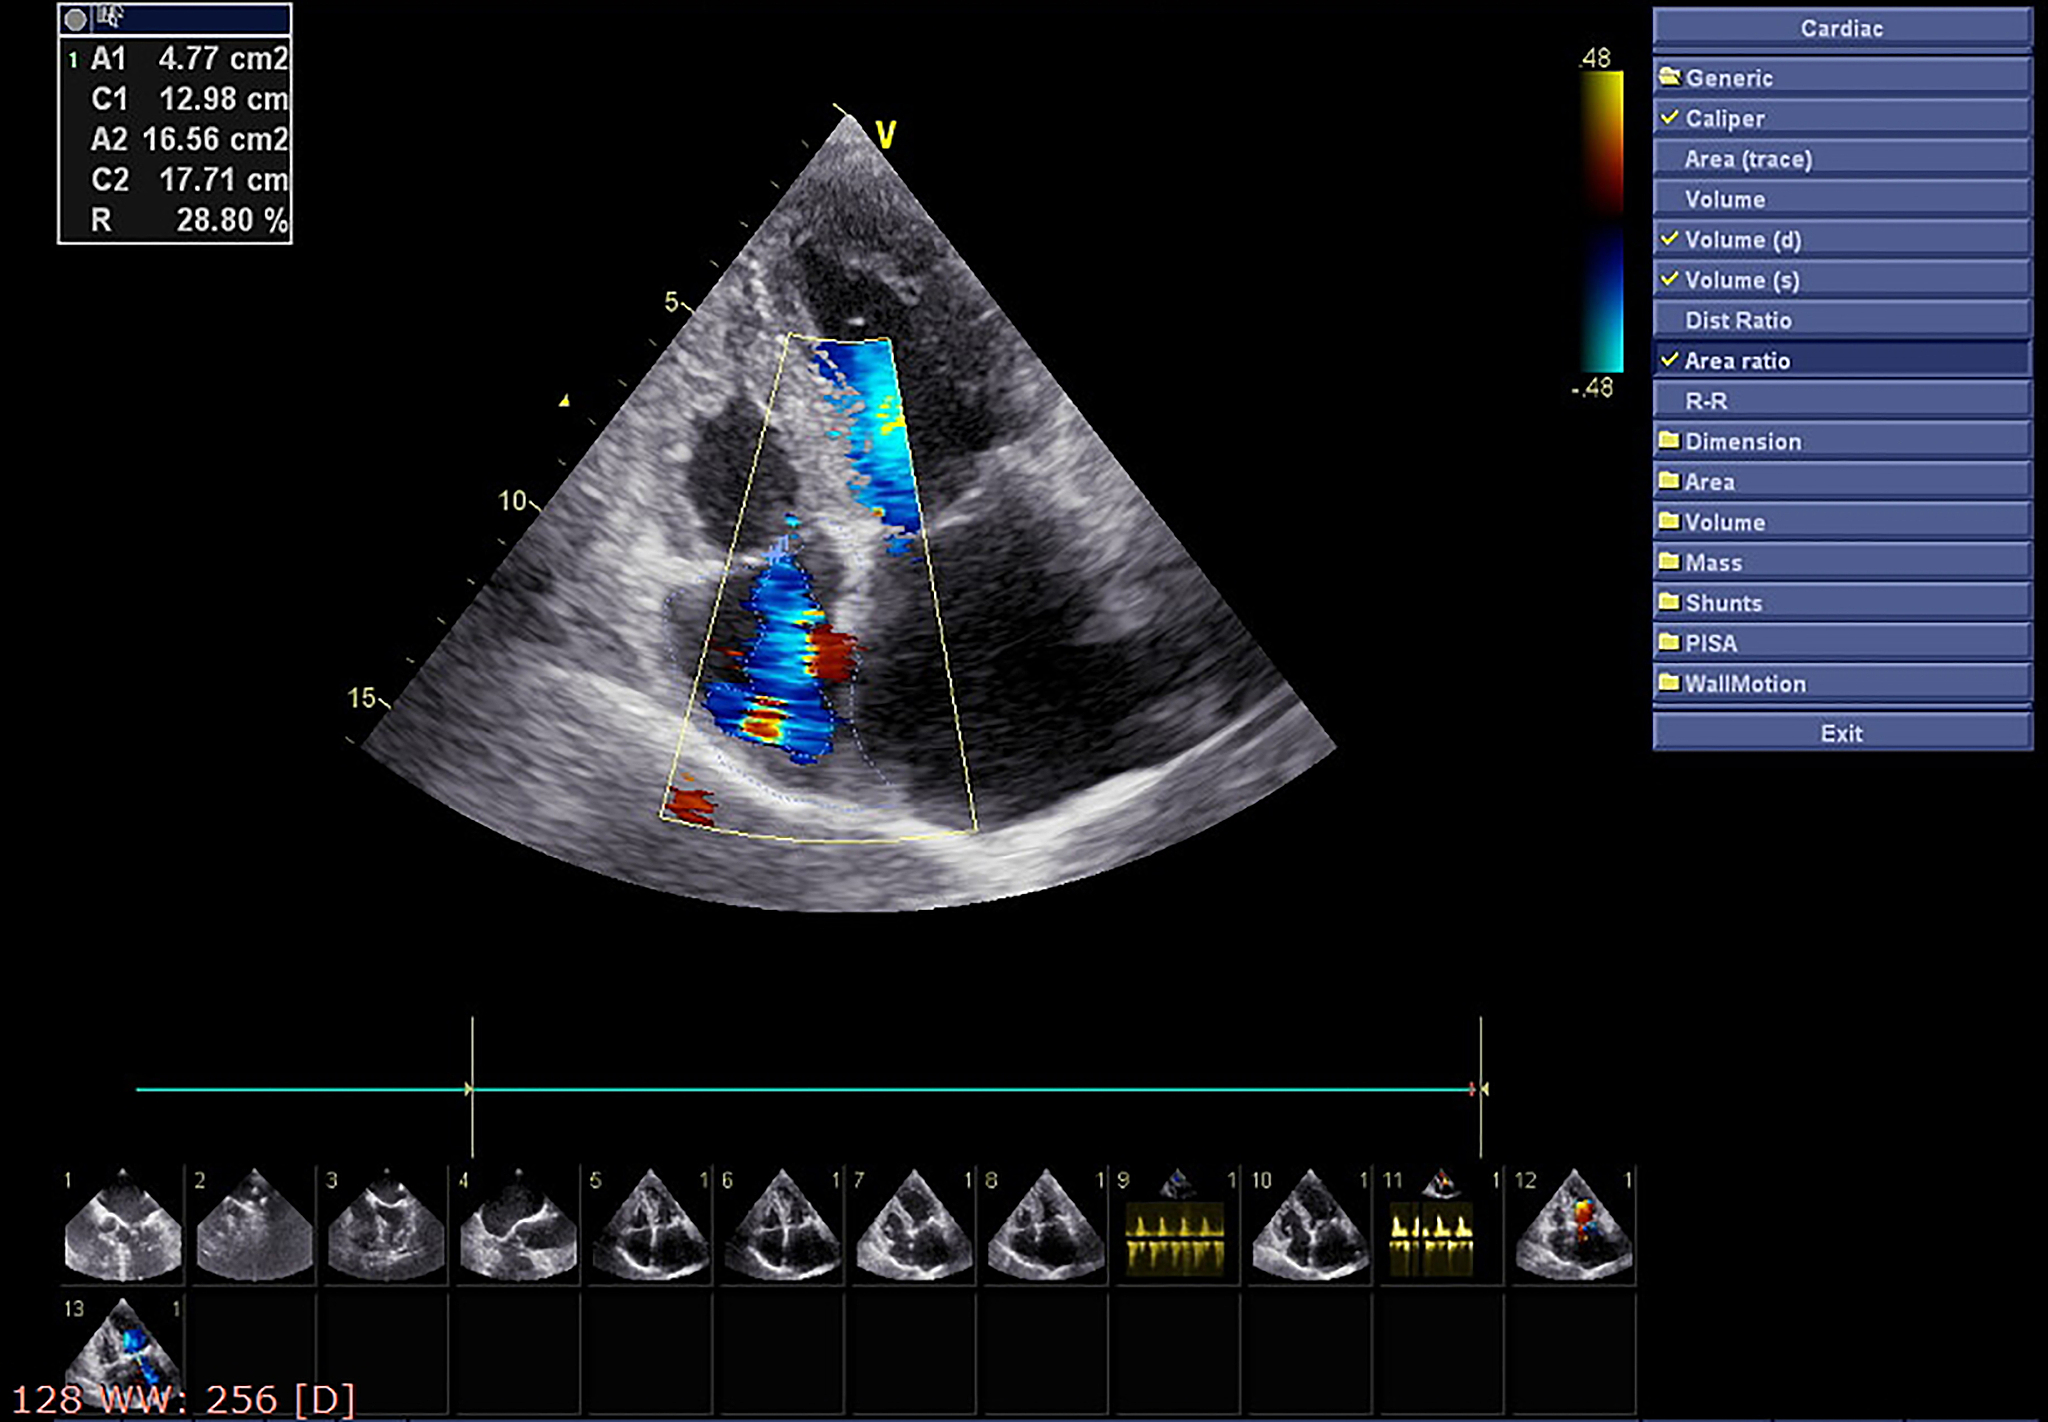

心脏瓣膜病是一种常见的心脏疾病,它涉及到心脏的瓣膜结构和功能异常。这些病变可能导致瓣膜狭窄、关闭不全或开放不全等问题,从而影响心脏的正常血液循环。超声诊断是一种非侵入性、安全可靠的诊断方法,通过使用超声波技术,我们可以直观地观察和评估心脏瓣膜的结构和功能。

在本课程中,我们将介绍心脏瓣膜病的常见类型,包括二尖瓣病变、主动脉瓣病变、三尖瓣病变和肺动脉瓣病变。我们将学习如何使用超声波技术来检测和评估这些病变,包括测量瓣膜的开闭情况、评估血液流速、观察瓣膜的结构和功能等。

此外,我们还将学习如何解读超声图像,识别不同病变的特征,以及如何与其他临床表现和检查结果相结合进行综合分析和诊断。通过学习本课程,您将能够熟练掌握心脏瓣膜病超声诊断的基本原理和技巧,并能够在临床实践中应用所学知识。